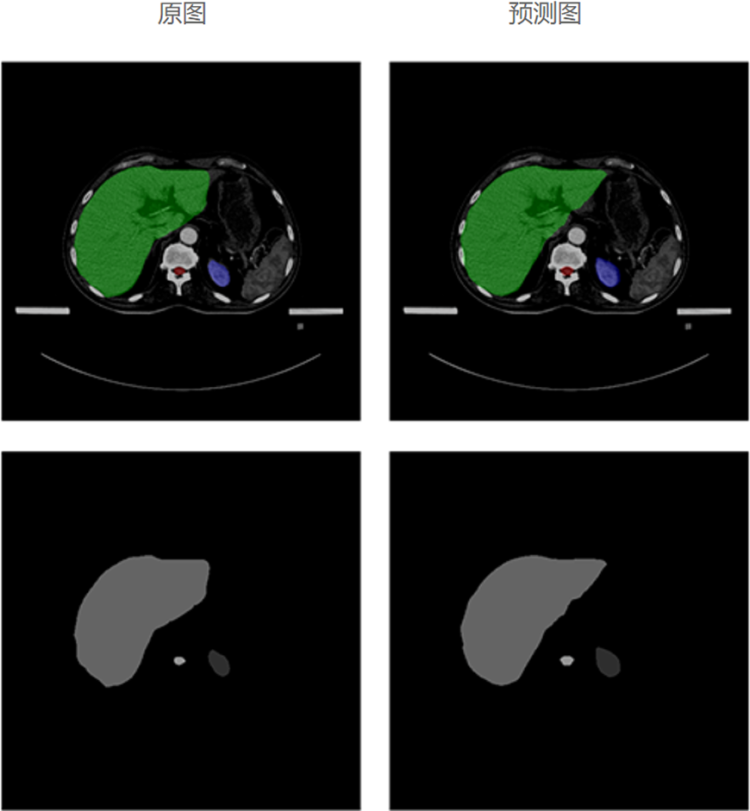

自动勾画效果

基于海量优选的专家勾画结构数据,利用深度学习人工智能技术,大力发展放疗智能勾画,自动勾画出精准且符合病人个性化特性的结果,帮助医生更加快速、准确地勾画肿瘤靶区和危及器官,从而推动放疗乃至肿瘤医疗的精准化、智能化发展,大大提高放疗勾画的工作效率。

模型经过对海量勾画结构数据的学习,以及改进优化,再进过大量样本数据训练及验证,自动勾画结果的平均准确度已达92%以上。